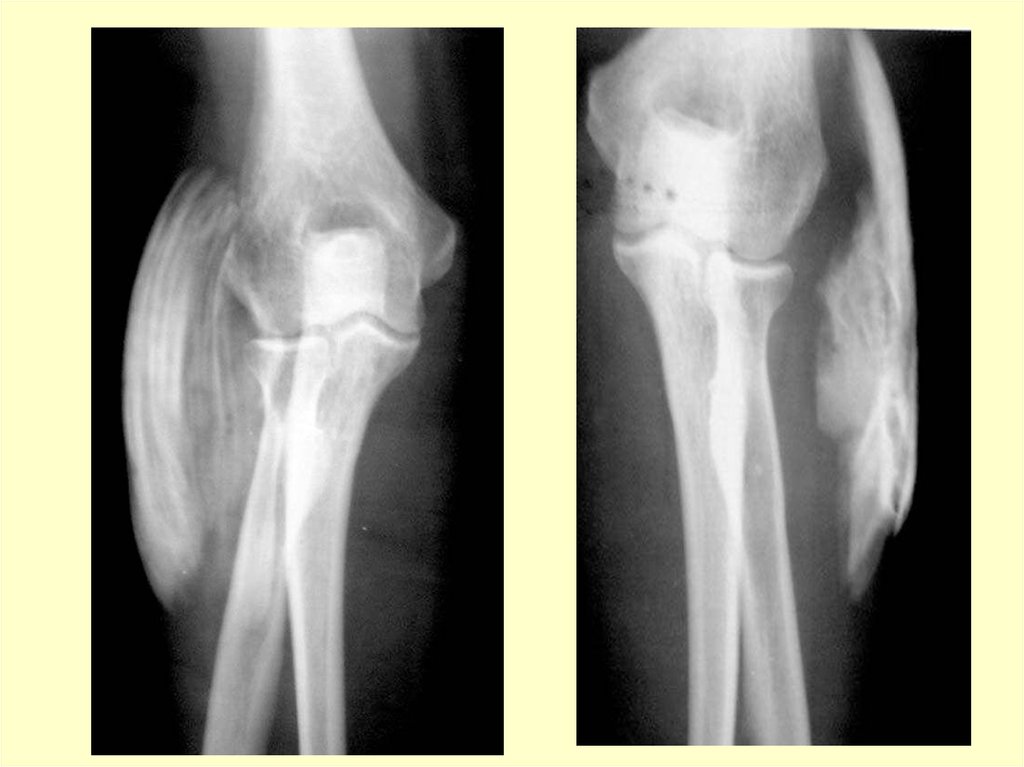

Экспертиза трудоспособности

16. Рентгенография

• При длительно текущем заболевании

на рентгенограммах удается

обнаружить очаги уплотнения

различной формы и размеров у контура

наружного надмыщелка.

• Реже обнаруживаются участки

резорбции (т.е. рассасывания) края

надмыщелка.